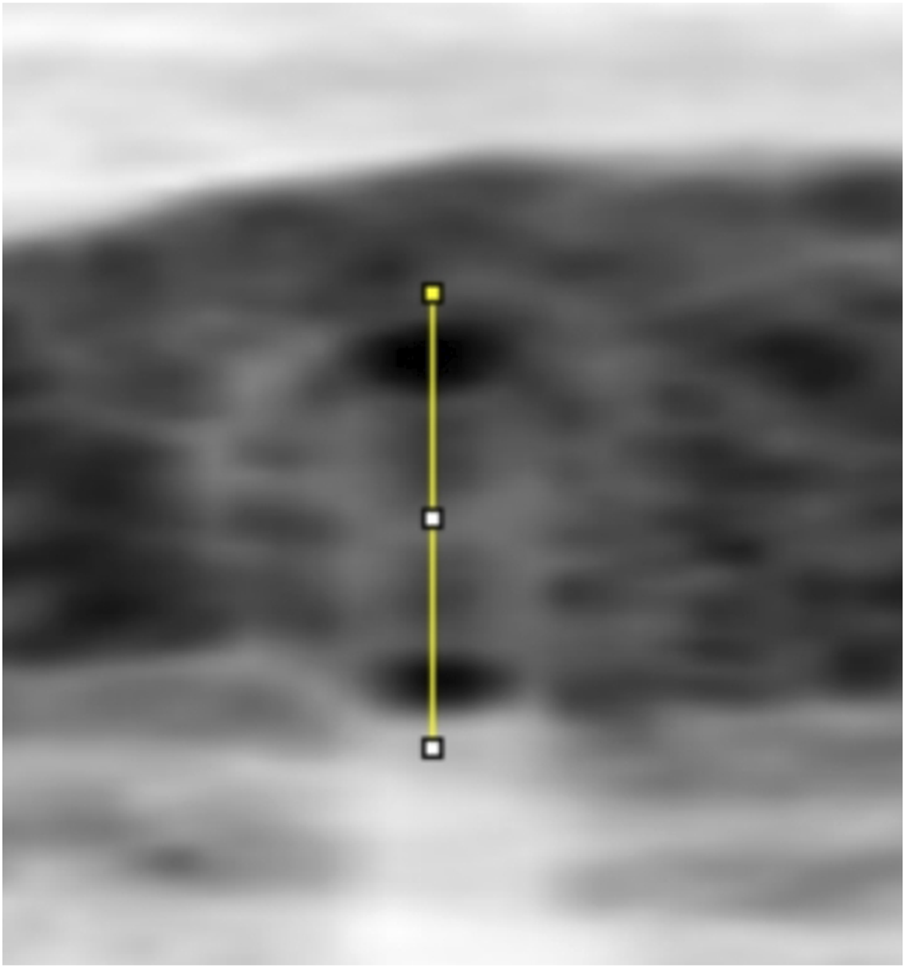

FIGURE 4

A line through the centre of the circle drawn between the upper and lower walls of a vessel to produce a greyscale density curve of the vessel wall.